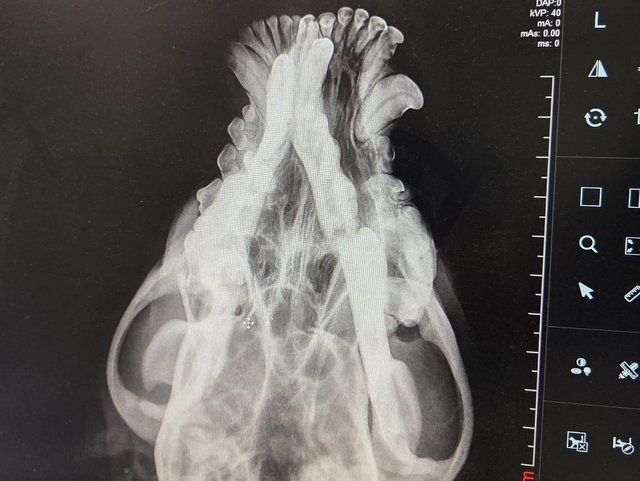

Camush Kopf ist wieder symmetrisch, der Kiefer wird jetzt mit Platte und Verdrahtung zusammengehalten und ein paar Zähne fehlen jetzt.

Röntgenbilder zeigten das Ausmaß der Zerstörung des Unterkiefers und den Bruch eines Beines.

Dieser Hund muss grausame Schmerzen haben, Zähne sind aus der Verankerung gerissen und sein Gesichtsschädel ist nicht mehr symmetrisch. Ein großes Stück des Unterkiefers ist komplett abgebrochen.

Es braucht sicher viel Geschick, um das wieder so zusammenzusetzen, dass der Hund später problemlos fressen kann.